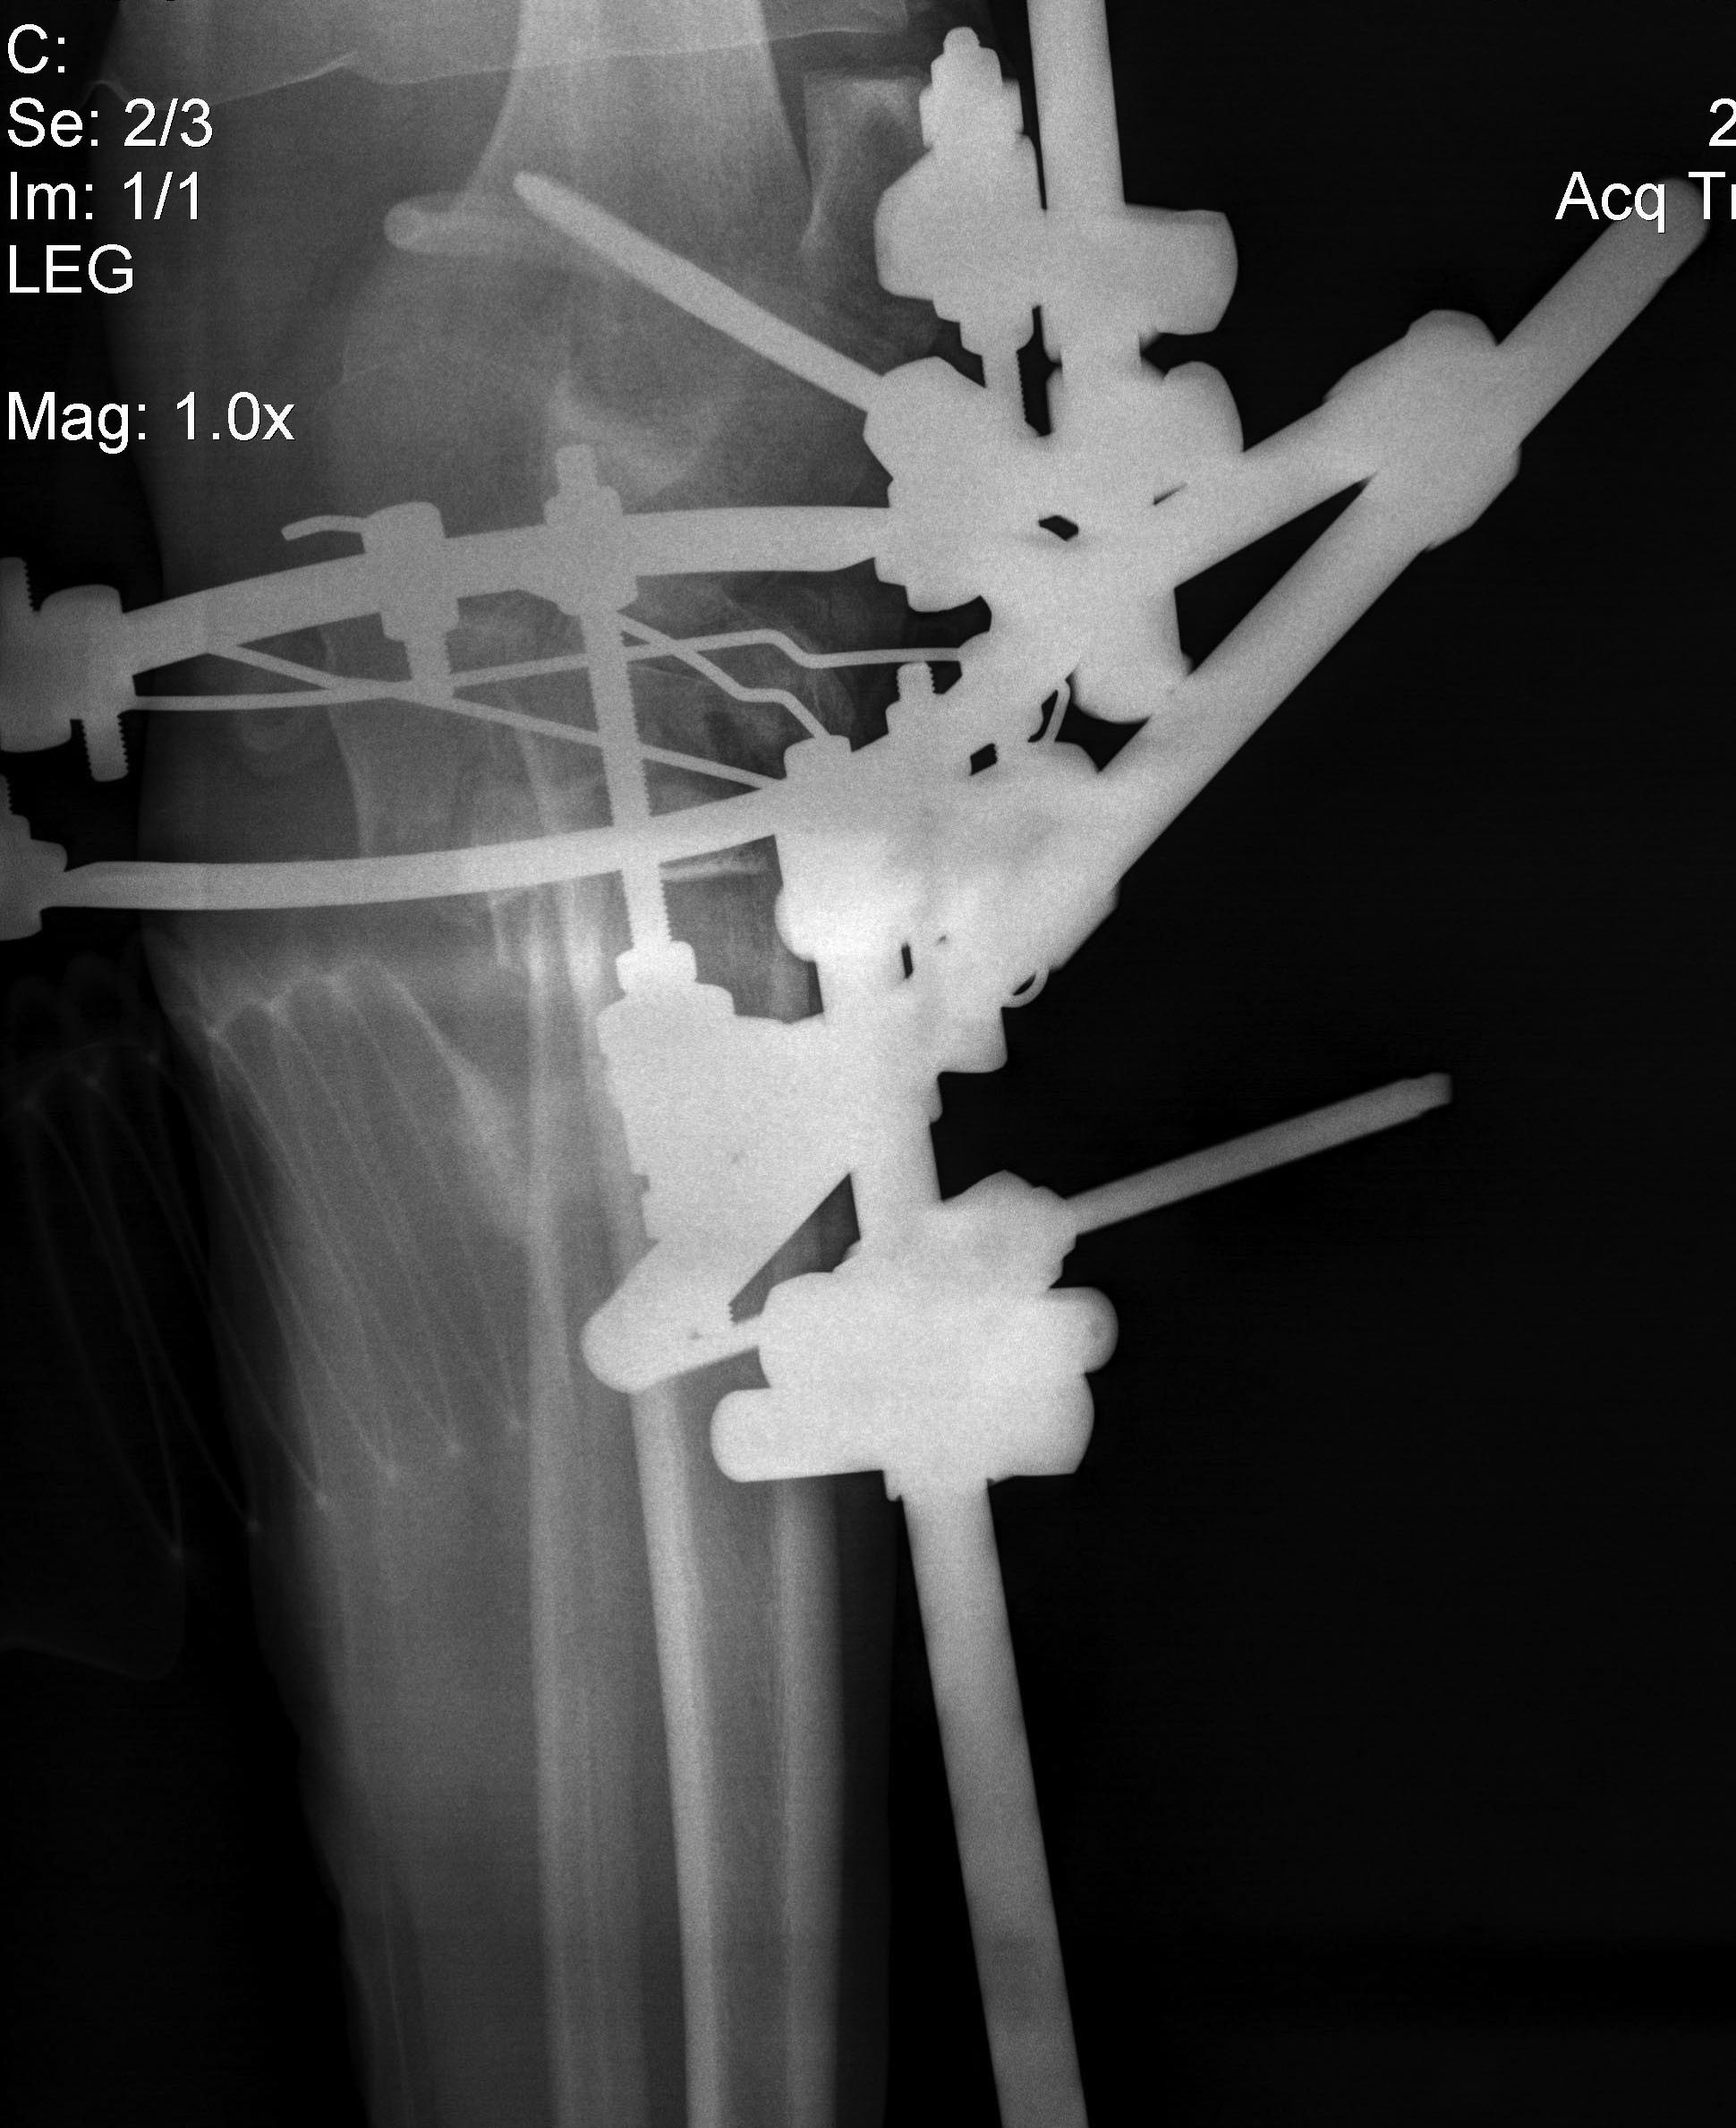

Имеется: Закрытый перелом диафиза левой локтевой кости. Закрытый оскольчатый перелом диафиза левой бедренной кости в средней трети. Открытые (3a-b) оскольчатые внутрисуставные переломы проксимального отдела обеих костей правой и левой голени. (см. снимки)

При поступлении выполнено: ПХО открытых перелом костей правой и левой голени, фиксация в аппаратах; фиксация перелома левой бедренной кости в аппарате; иммобилизация левого предплечья лонгетой.

Планируем: при неосложненном заживлении, остеосинтез правой большеберцовой кости пластиной; остеосинтез бедренной кости стержнем; локтевой кости пластиной.

Что делать с переломами костей левой голени пока не решили окончательно. Пока мнение коллег такое: оставить все как есть до заживления /консолидации и ортопедические проблемы с коленным суставом и укорочением (3-4 см) решать в отдаленном периоде – эндопротезирование (?).